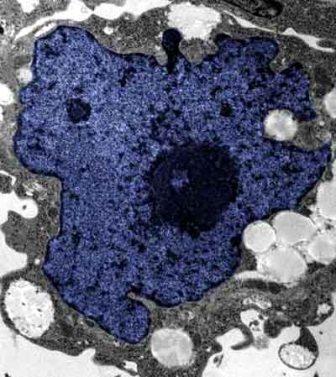

在成人體內(nèi)及胚胎內(nèi)發(fā)現(xiàn)的干細(xì)胞屬于主細(xì)胞,能發(fā)育成各種各樣的組織,可作為人體“修補(bǔ)工具箱”,取代死去及腐壞細(xì)胞組織。此前,最可行的干細(xì)胞為胚胎干細(xì)胞,但它的使用一直受到爭議,因?yàn)橐谂咛コ槿「杉?xì)胞會(huì)令胚胎死亡,有人認(rèn)為這樣是變相奪走一條生命。

來自英國和加拿大的兩組研究員所用的新方法不必使用病毒。這項(xiàng)新突破暗示科學(xué)家現(xiàn)在能更認(rèn)真地看待在醫(yī)學(xué)中利用皮膚干細(xì)胞(即誘導(dǎo)多功能干細(xì)胞,俗稱“iPs”細(xì)胞)的前景。

這些細(xì)胞只要配以適當(dāng)?shù)幕瘜W(xué)品和蛋白質(zhì),就能轉(zhuǎn)化成腦神經(jīng)元、制造胰島素的胰腺細(xì)胞、骨或軟骨、心臟肌肉,或其它多種組織。這些細(xì)胞利用病人皮膚來培育,更暗示它們不會(huì)被人體排斥。